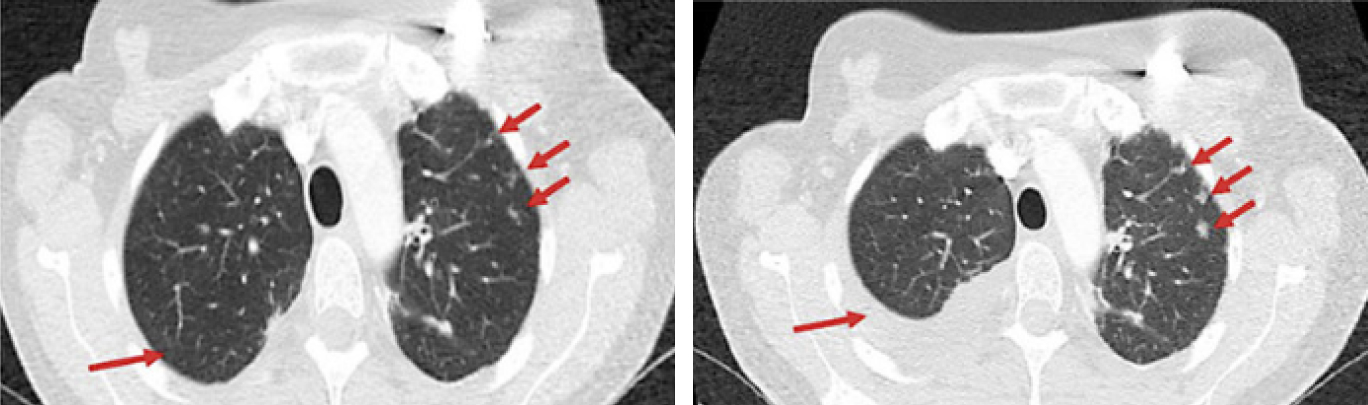

При очередном контрольном обследовании отмечено прогрессирование заболевания в виде значимого роста метастатических очагов в легких на 30% в сравнении с nadir по RECIST 1,1, а также отмечается появление правостороннего гидроторакса. Пациентка осмотрена хирургом, показаний для торакоцентеза в настоящее время не выявлено.

Рис. 1 — динамика заболевания на фоне проведения гормонотерапии ингибиторами ароматазы, разница в сроках исследования — 4 месяца.